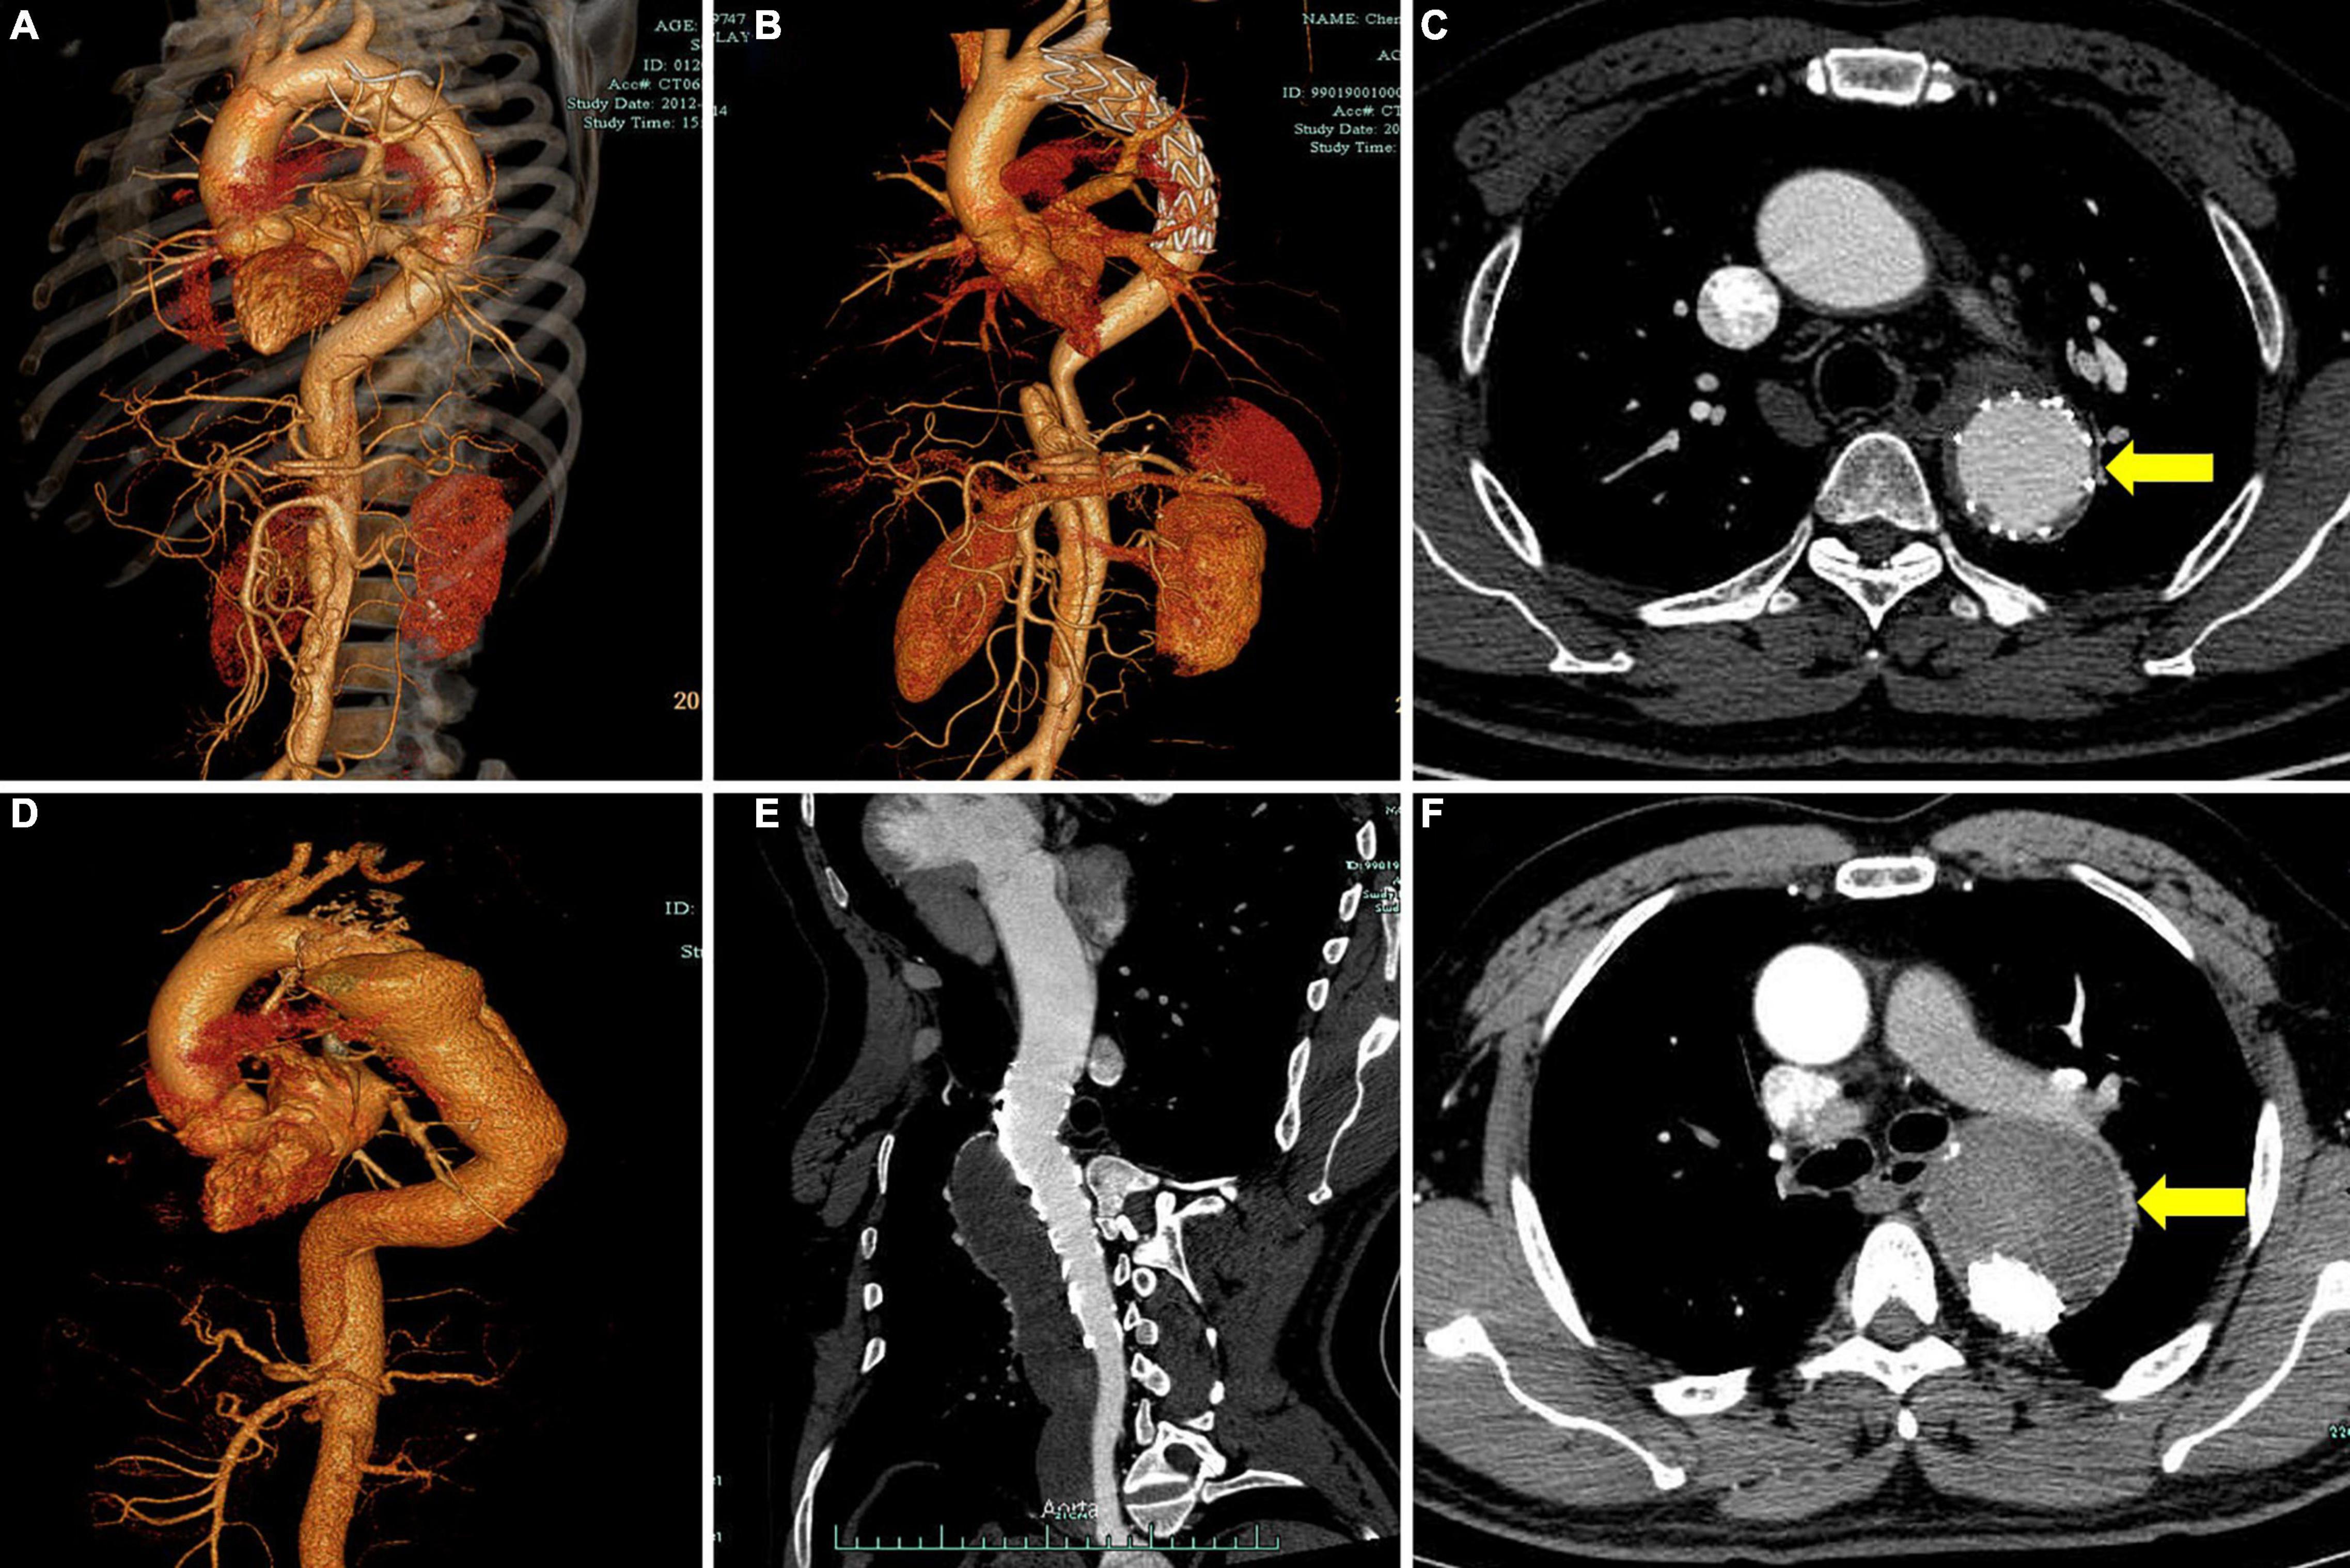

FIGURE 2

Figure 2. Representative cases of different degrees of FL thrombosis after TEVAR. Computed tomography angiography (CTA) images show the FL status of a patient with subacute aortic dissection before operation (A) and 2 years after TEVAR (B). The cross-sectional image shows complete obliteration of FL (C, yellow arrow). CTA images show the FL status of a patient with chronic aortic dissection before operation (D) and 2 years after TEVAR (E). The cross-sectional image shows total FL thrombosis (F, yellow arrow). FL, false lumen; TEVAR, thoracic endovascular aortic repair.